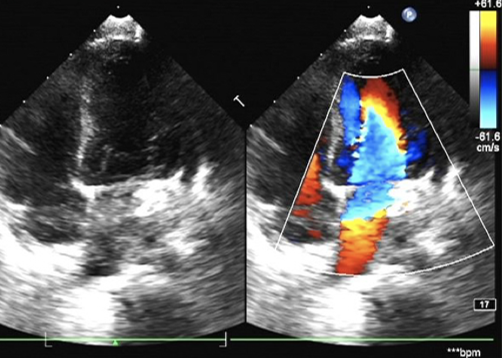

心脏彩超:LV 25 mm,LA 18 mm,RV 11 mm,RA 20 mm;EF 70%,FS 38%。左冠状动脉开口增粗,内径约7 mm,走行迂曲,回旋支增粗,瘘入冠状静脉窦,瘘口径约6 mm,瘘口处频谱呈双期湍流,Vmax=1.6 m/s;冠状静脉窦明显增粗,内径约10 mm,其右房开口径约5.7 mm,频谱呈双期高速湍流,Vmax=5.4 m/s。

术后一月后心脏彩超:冠状静脉窦(邻近右房入口处)内探及封堵器回声,位置固定。回旋支-冠状静脉窦封堵器周未见明显分流。